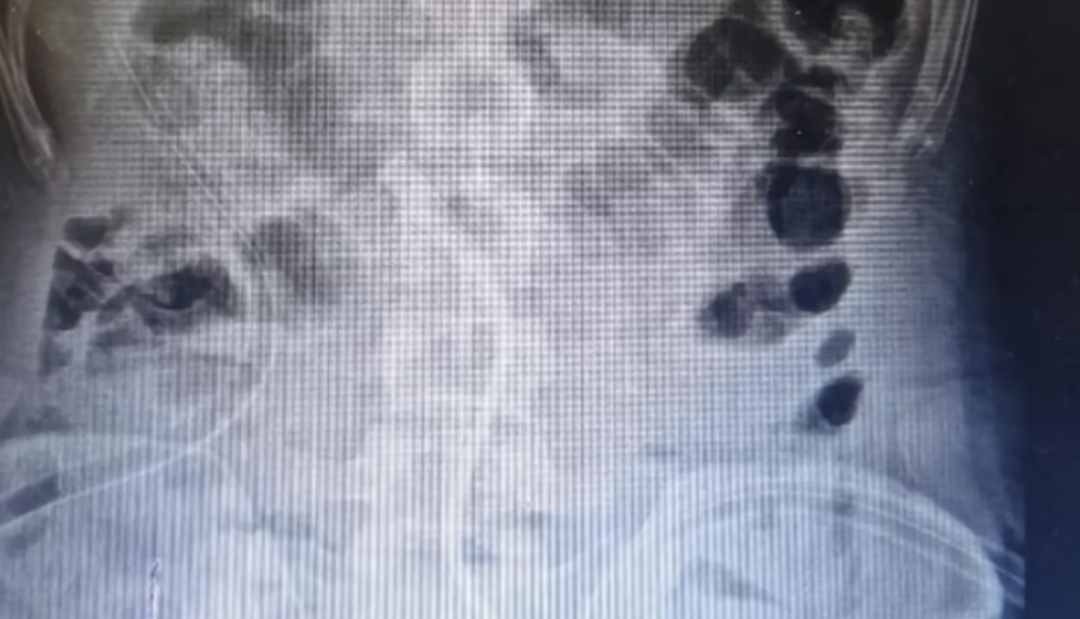

Un hombre de 26 años acudió al Hospital Sir Ganga Ram, ubicado en Nueva Delhi, India por intensos dolores y abdominales y vómitos. Al practicarle radiografías y demás exámenes encontraron diversas piezas de metal incrustadas en sus intestinos.

Tras estos alarmantes resultados, el paciente fue remitido de urgencia a cirugía, en donde se descubrió que 37 imanes y 39 monedas estaban alojadas en sus paredes abdominales y el intestino delgado que no fueron expulsadas de forma natural pues la fuerza magnética entre ellas causó un bloqueo en los bucles del intestino. La razón por la cual lo hizo, declaró el paciente, es que creía que el zinc ayudaba a construir un mejor físico y alcanzar sus metas como fisicoculturista.